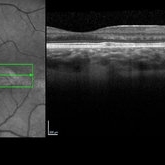

SD-OCT - Torpedo Maculopathy

SD-OCT through lesion at posterior pole of asymptomatic 8-year-old female.

Condition/keywords: torpedo maculopathy